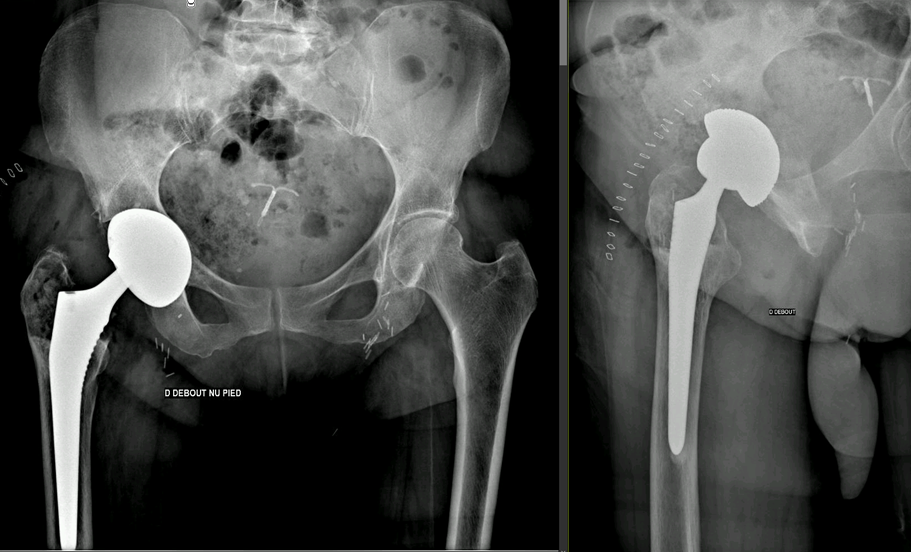

Full weight-bearing was allowed immediately postoperatively. At discharge, five days after surgery, the patient reported no squeaking, was pain-free, and was ambulating independently with a single crutch. Postoperative radiographs are shown in Figure 5.

Figure 5. Postoperative anteroposterior pelvic and lateral right hip radiographs, 2024.